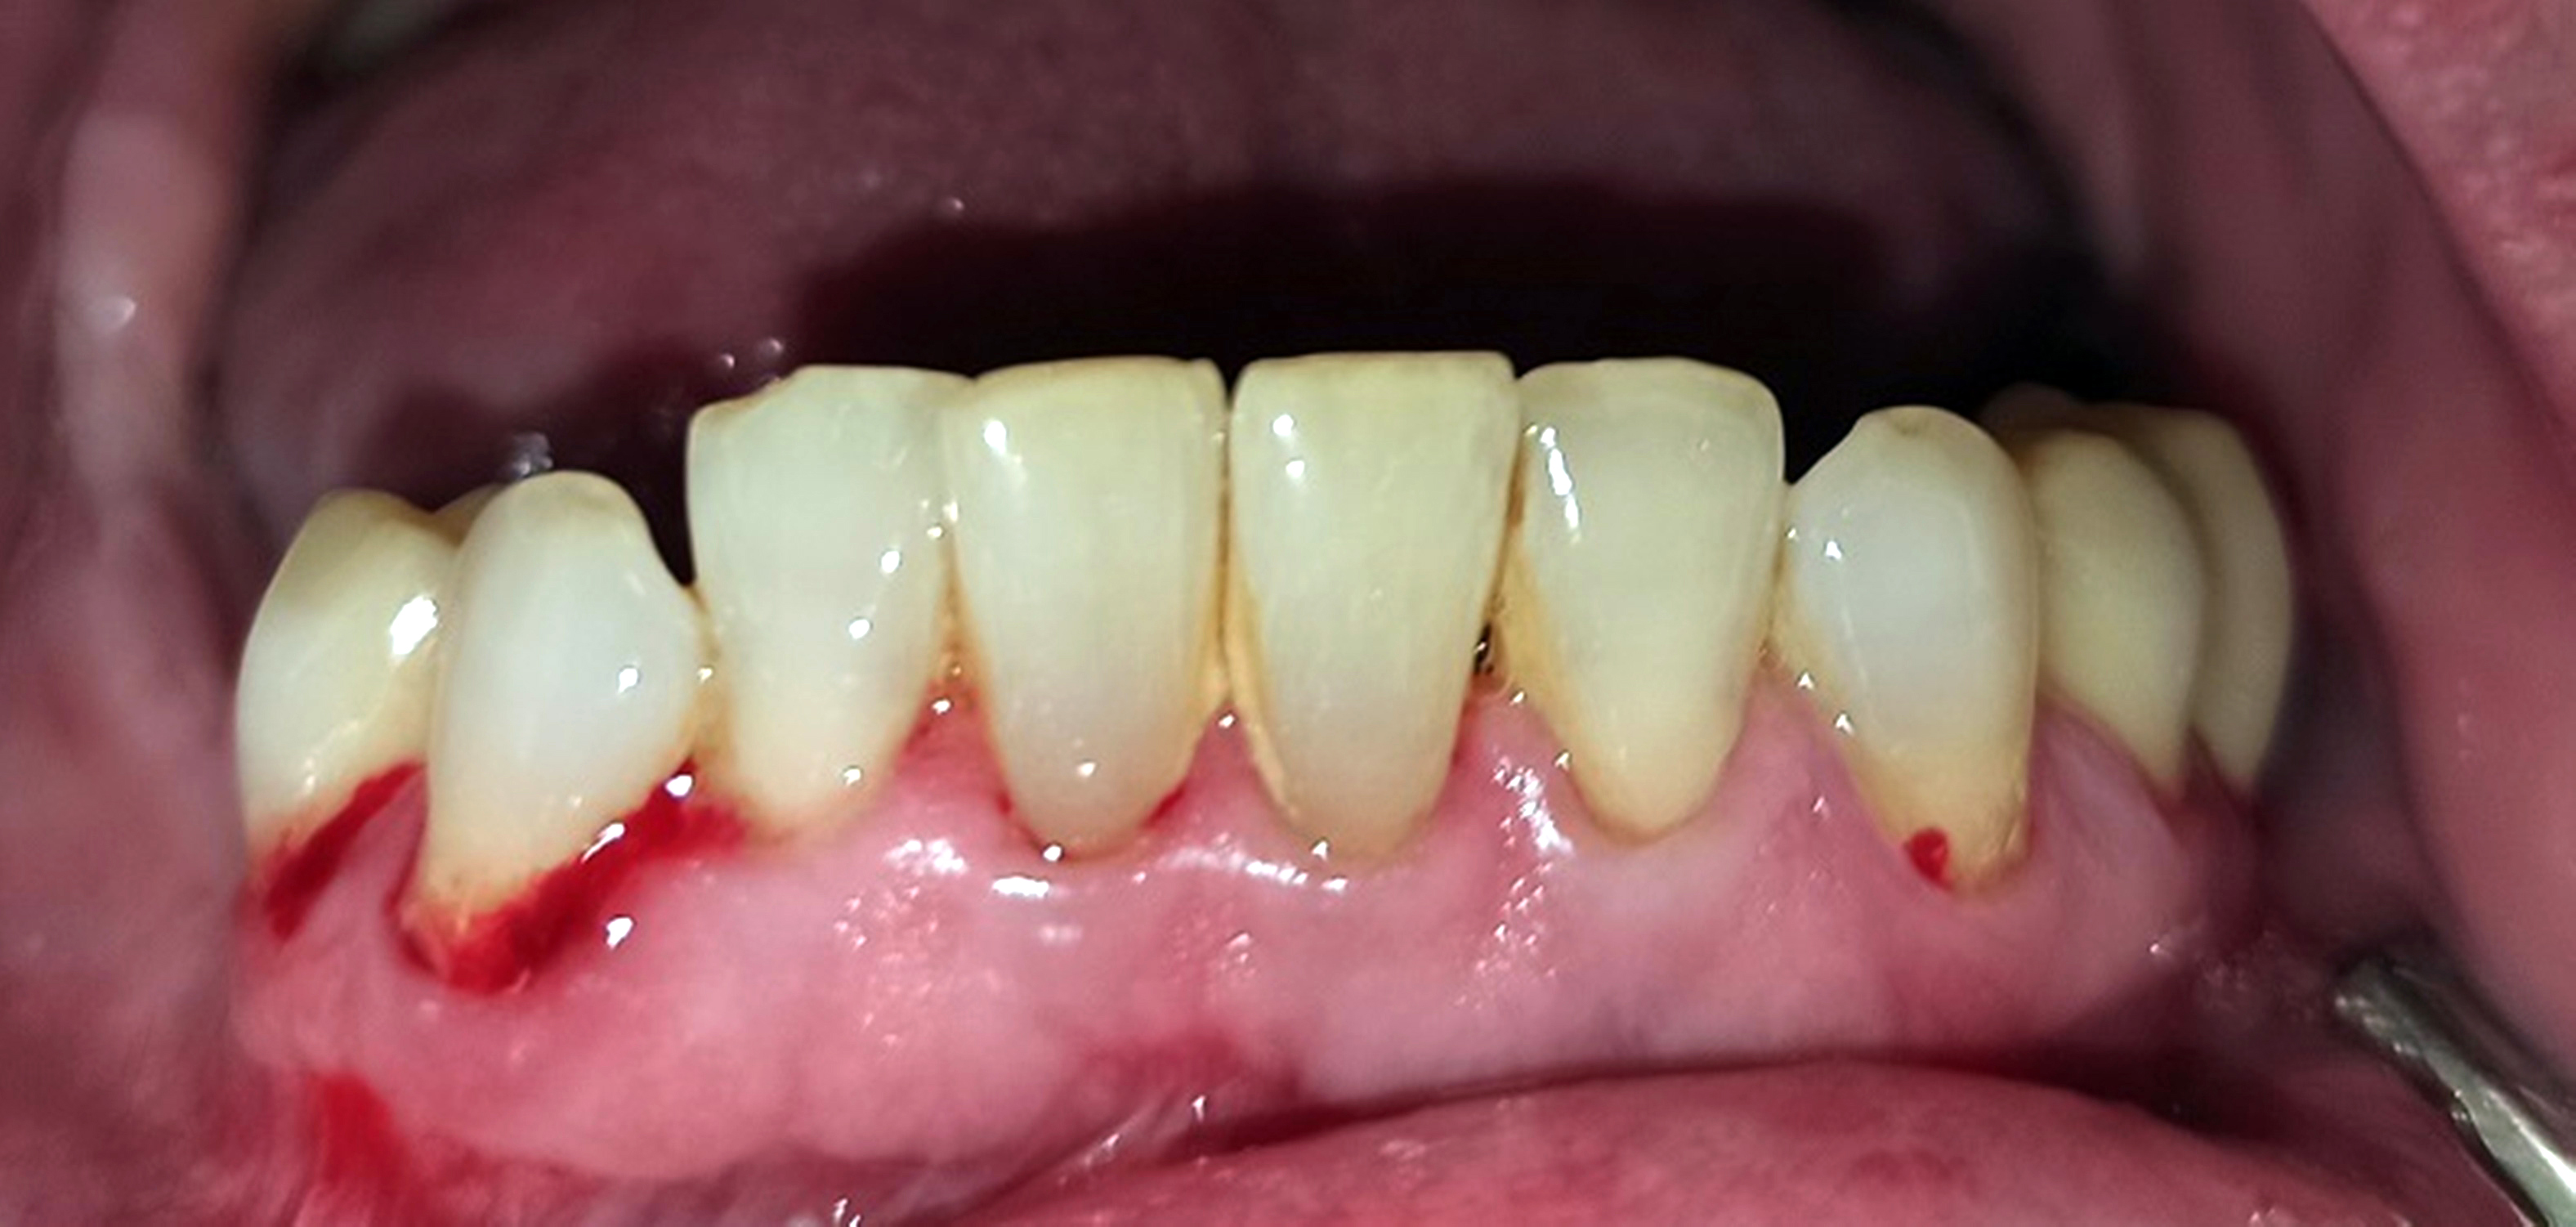

Innerhalb der Gruppe der Patienten mit Fazialisparese wurde außerdem ein Vergleich der Mundgesundheit zwischen beiden Mundhälften durchgeführt. Dabei wies die paretische Seite eine signifikant höhere Plaque-Kontamination, mehr Blutungen und höhere PSI-Werte auf als die nicht paretische Seite (Tab. 3). Die Plaque-Kontamination war in Bezug auf den API auf der paretischen Seite um 10,9 % (p = 0,004) höher als auf der nicht paretischen Seite. Ebenso wiesen die vestibulären Zahnoberflächen der paretischen Seite mehr Biofilm auf als die der nicht paretischen Seite (p = 0,002; s. Tab. 3, Abb. 2a und b). Dabei war der Unterschied bei den männlichen Patienten (0,8 vs. 0,5; p = 0,001) größer als bei den weiblichen Patienten (0,6 vs. 0,4; p = 0,002). Außerdem wurde bei Patienten mit rechtsseitiger Fazialisparese ein größerer Seitenunterschied (0,7 vs. 0,5; p < 0,001) dokumentiert als bei Patienten mit linksseitiger Fazialisparese (0,5 vs. 0,4; p = 0,043). Ursächlich erschien die Händigkeit der Patienten. Während bei Patienten mit linksseitiger Fazialisparese die Erkrankung auf der für Rechtshänder besser zu reinigenden Mundhälfte vorlag, waren rechtshändige Patienten mit rechtsseitiger Fazialisparese einer doppelten Belastung ausgesetzt (18). Die Gingivablutung nach Sondierung war auf der paretischen Seite ebenfalls signifikant höher als auf der nicht paretischen Seite (s. Tab. 3). Das spiegelte sich sowohl bei den Werten des SBI (s. Tab. 3, Abb. 3) als auch bei den Werten des PBI (s. Tab. 3, Abb. 4a und b) wider. Die Sondierungstiefen waren auf der paretischen Seite im Vergleich zur nicht paretischen Seite tiefer und der Attachmentverlust war höher. Dabei konnte jedoch kein signifikanter Unterschied nachgewiesen werden. Der mittlere PSI erreichte auf der paretischen Seite signifikant höhere Werte als auf der nicht paretischen Seite (p = 0,032; s. Tab. 3), was auf eine schlechtere Gingivagesundheit hinweist. Darüber hinaus war die Prävalenz unbehandelter kariöser Läsionen auf der paretischen Seite höher als auf der nicht paretischen Seite (s. Tab. 3). Ein Fallbeispiel illustriert eindrucksvoll die Unterschiede zwischen der kariesfreien nicht paretischen Seite und der paretischen Seite mit multiplen aktiv kariösen Läsionen (Abb. 5a und b). Zusätzlich wies die paretische Seite eine höhere Anzahl an Restaurationen auf als die nicht paretische Seite (s. Tab. 3). Hinsichtlich des Zahnsteinbefalls wurden auch im Seitenvergleich der Mundhälften keine signifikanten Unterschiede zwischen den paretischen und den nicht paretischen Seiten festgestellt. Im Einzelfall wurden jedoch eindrucksvolle Unterschiede zwischen den Mundhälften deutlich (Abb. 6a und b).